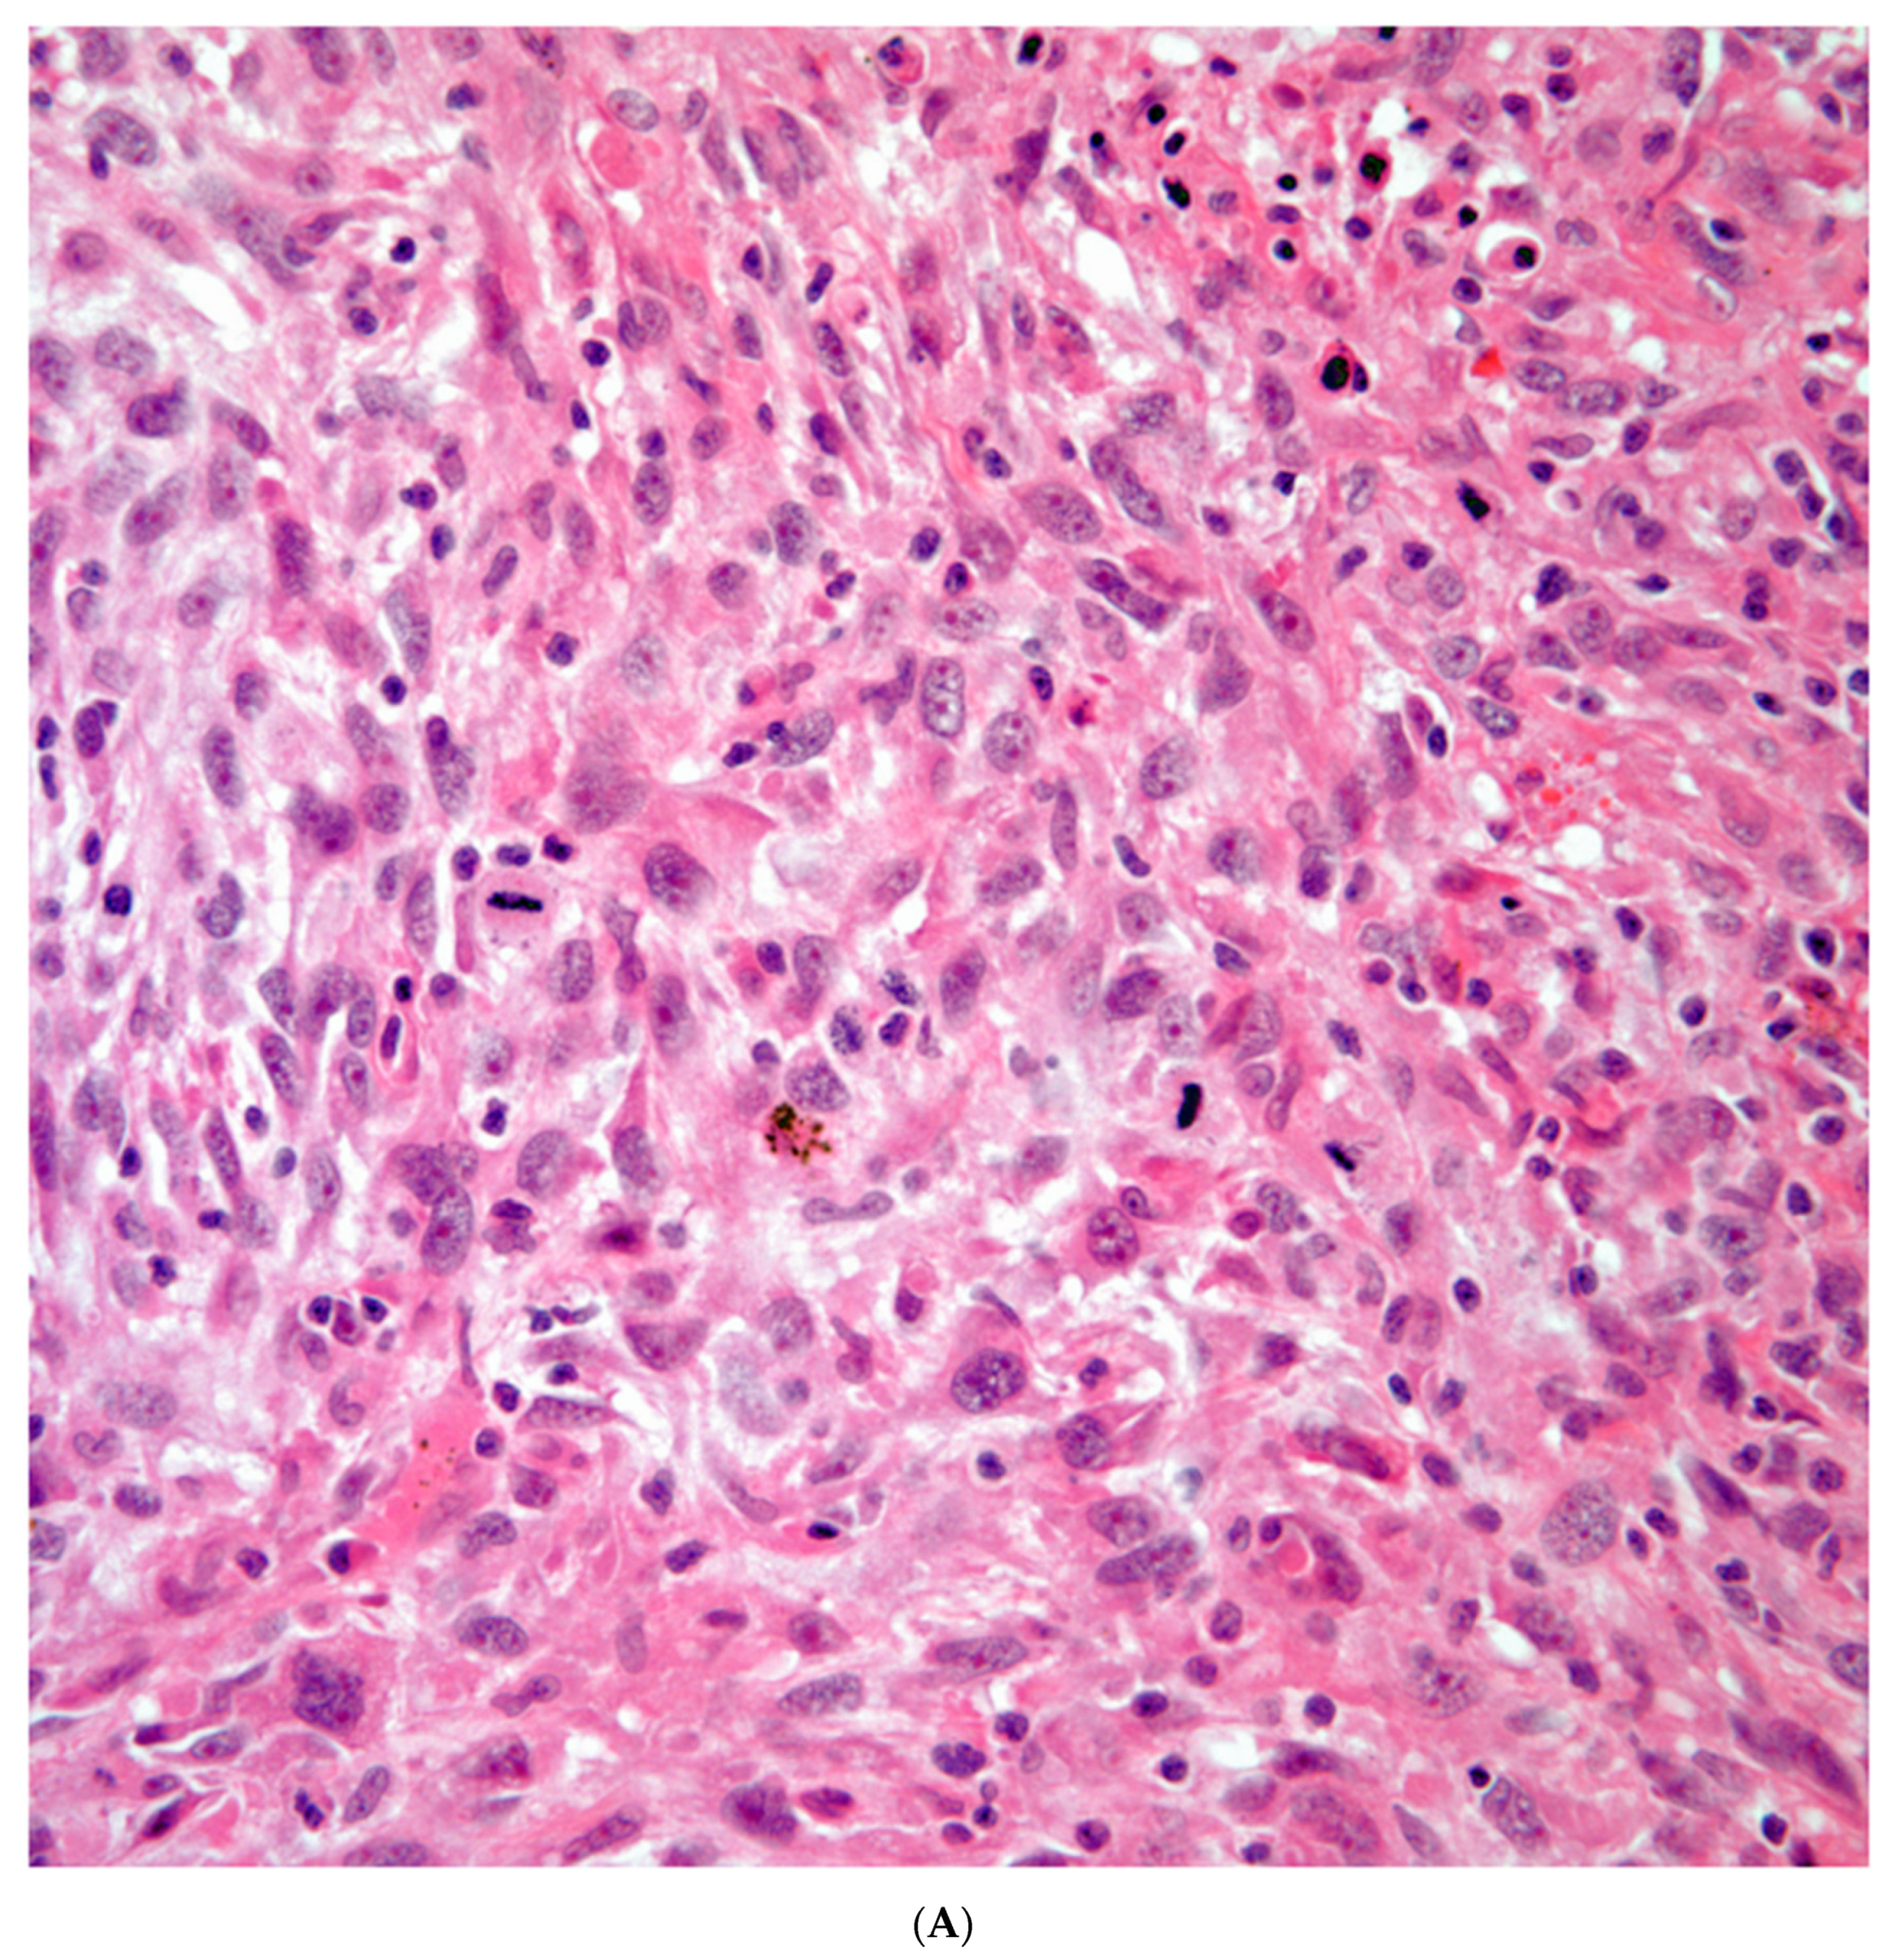

Sarcomatoid carcinomas: these tumors show a tightly packed spindle cell proliferation composed of slender cells with fusiform nuclei and inconspicuous nucleoli, replacing normal lung parenchyma. The tumors are well delimited but not encapsulated (Figure 1). Cellular atypia is variable and may show areas of mild to moderate to marked atypia. Mitotic figures also vary and may be inconspicuous or may be evident with the presence of atypical mitotic figures (Figure 2A,B). In high grade tumors, the presence of necrosis and hemorrhage is prominent and is mixed with the neoplastic component. Important to recognize is that sarcomatoid carcinomas may be associated with areas of otherwise conventional non-small cell carcinoma such as adenocarcinoma or squamous cell carcinoma (Figure 3A,B). In addition, sarcomatoid carcinoma may also show the presence of bizarre giant cells admixed with the spindle cell component (Pleomorphic carcinoma) (Figure 4).

Giant Cell Carcinomas: these tumors may show predominantly a neoplastic cellular proliferation composed exclusively of multinucleated giant cells or a predominantly giant cell carcinoma (Figure 5A,B) or associated with a conventional non-small cell carcinoma such adenocarcinoma or squamous cell carcinoma. The giant cell carcinoma may show giant cells of the syncytiotrophoblastic, osteoclastic, or null cell type. The giant cell carcinomas of the null cell type characteristically show a prominent inflammatory background and giant cells engulfing inflammatory cells (emperipolesis) (Figure 6A,B). The tumors composed of osteoclast-like giant cells show giant cells like those described in bone tumors (Figure 7A,B)

Figure 5. A) Predominantly giant cell carcinoma; B) Marked atypia and numerous multinucleated malignant giant cells.